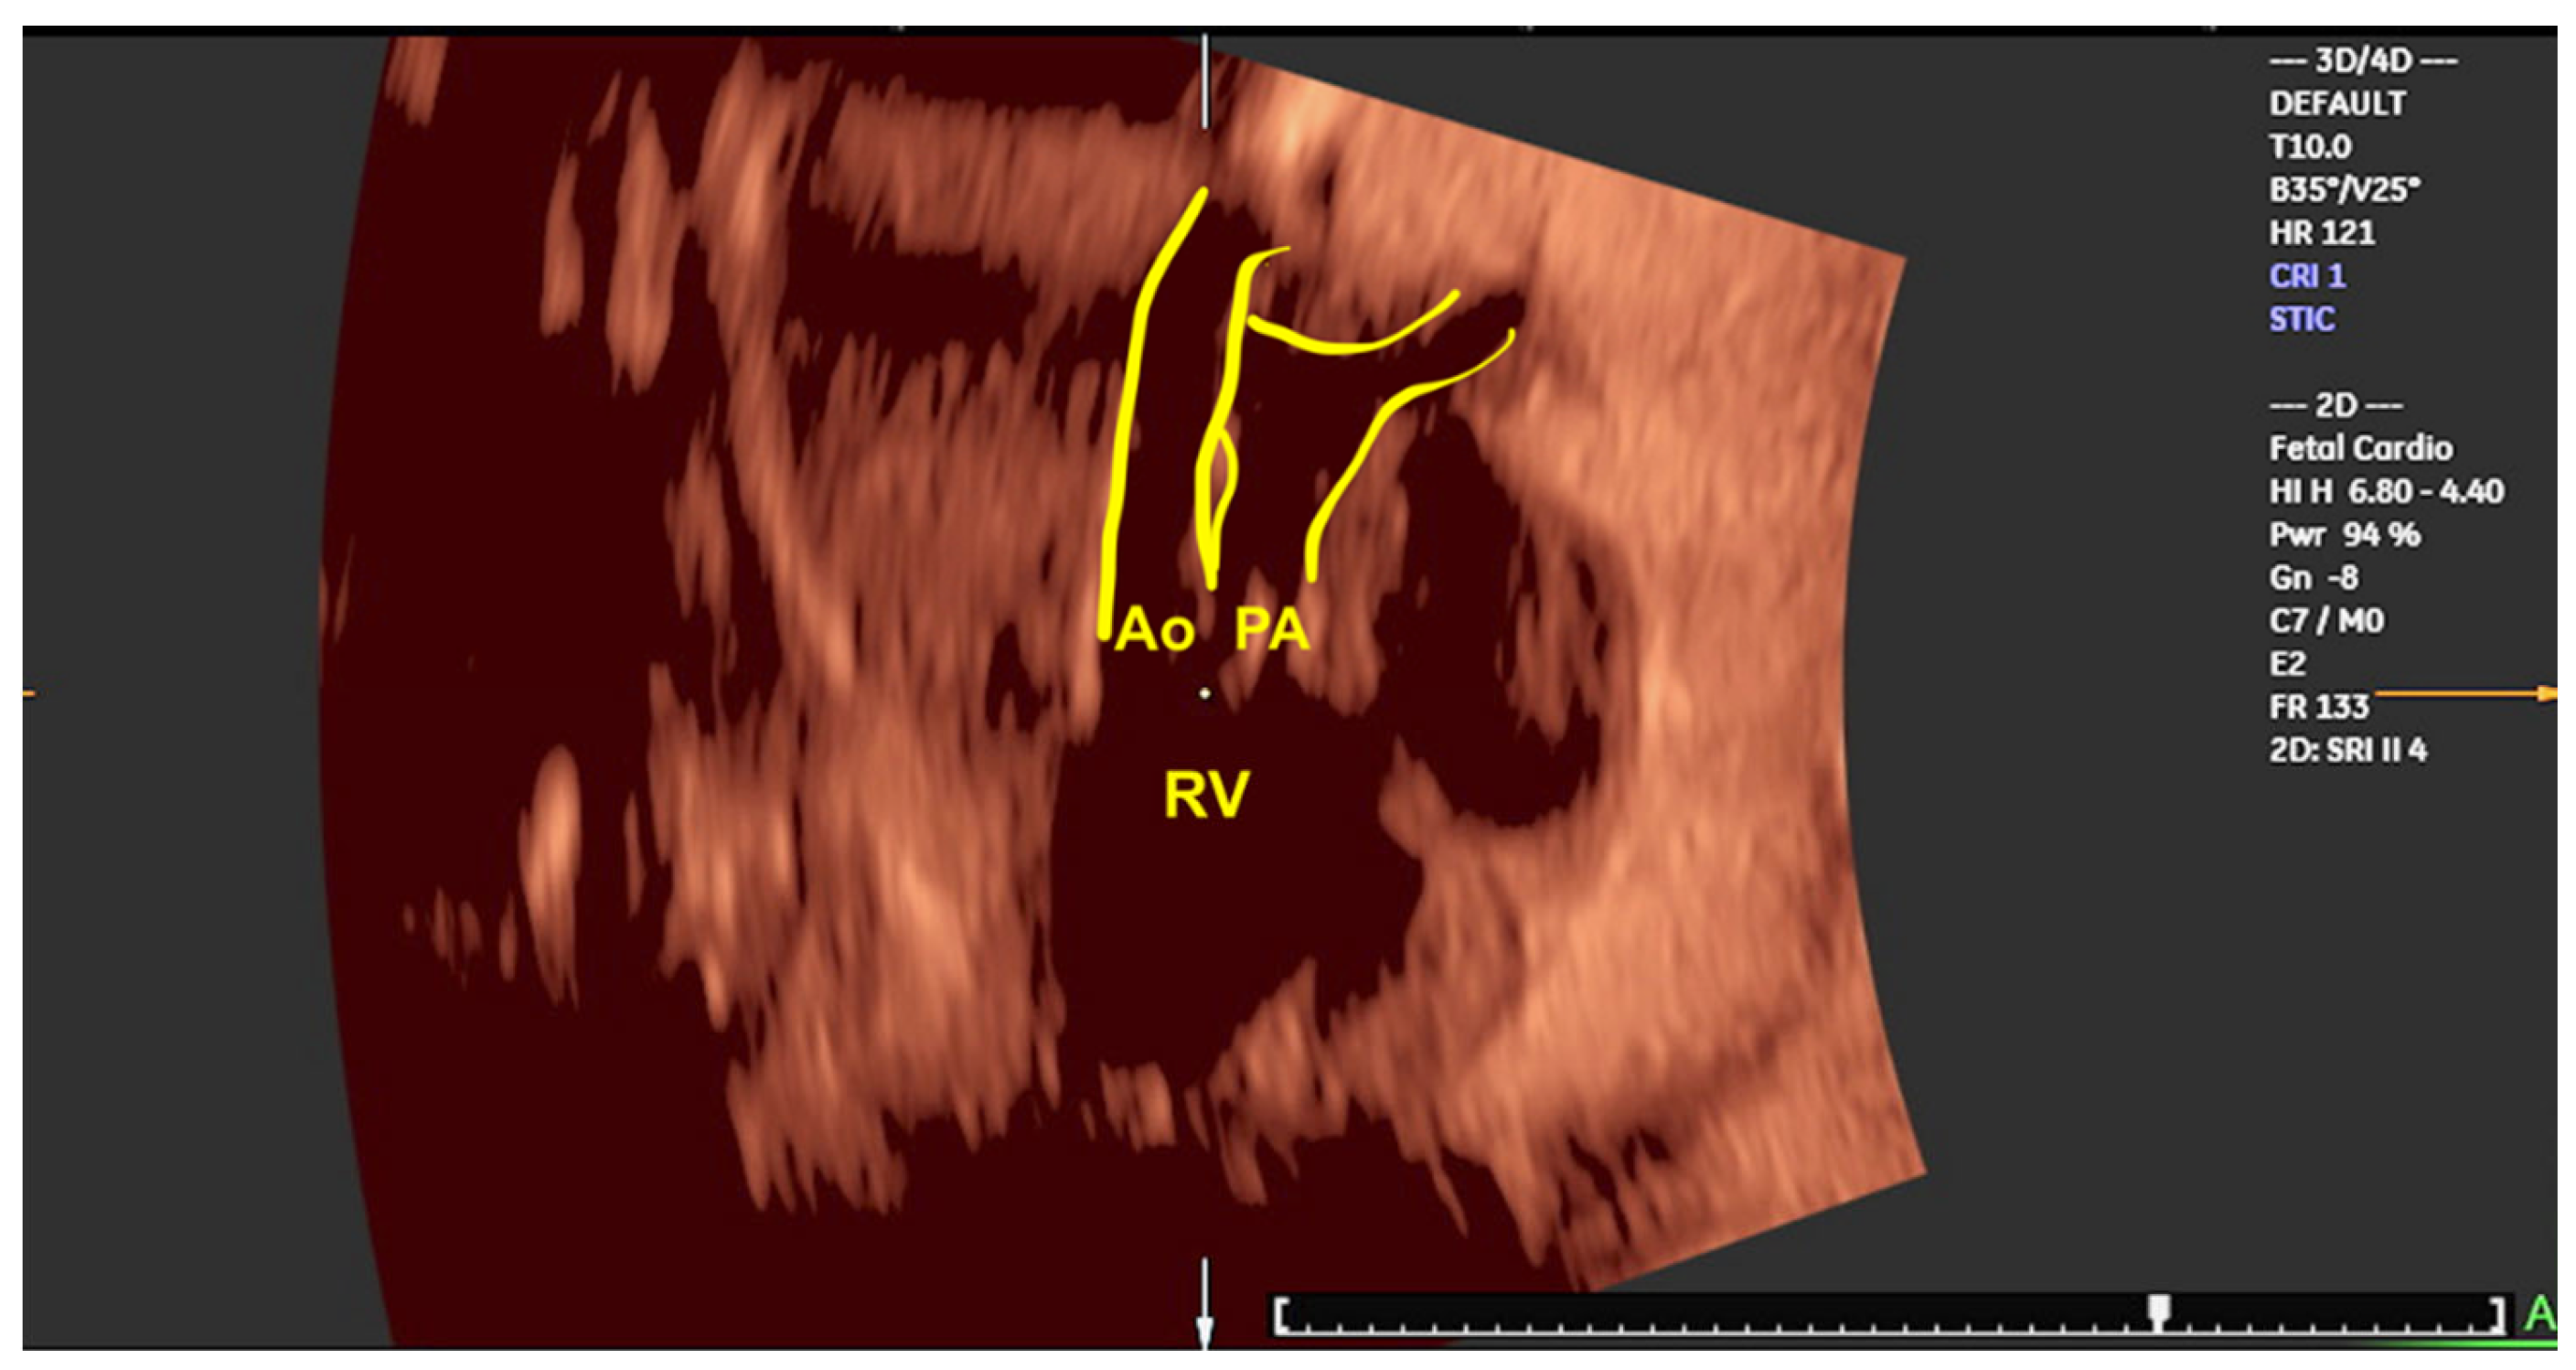

- Shih JC, Shyu MK, Su YN, Chiang YC, Lin CH, Lee CN. 'Big-eyed frog' sign on spatiotemporal image correlation (STIC) in the antenatal diagnosis of transposition of the great arteries. Ultrasound Obstet Gynecol. 2008, 32, 762–768.

- Araujo Júnior E, Tonni G, Bravo-Valenzuela NJ, Da Silva Costa F, Meagher S. Assessment of Fetal Congenital Heart Diseases by 4-Dimensional Ultrasound Using Spatiotemporal Image Correlation: Pictorial Review. Ultrasound Q. 2018, 34, 11–17.